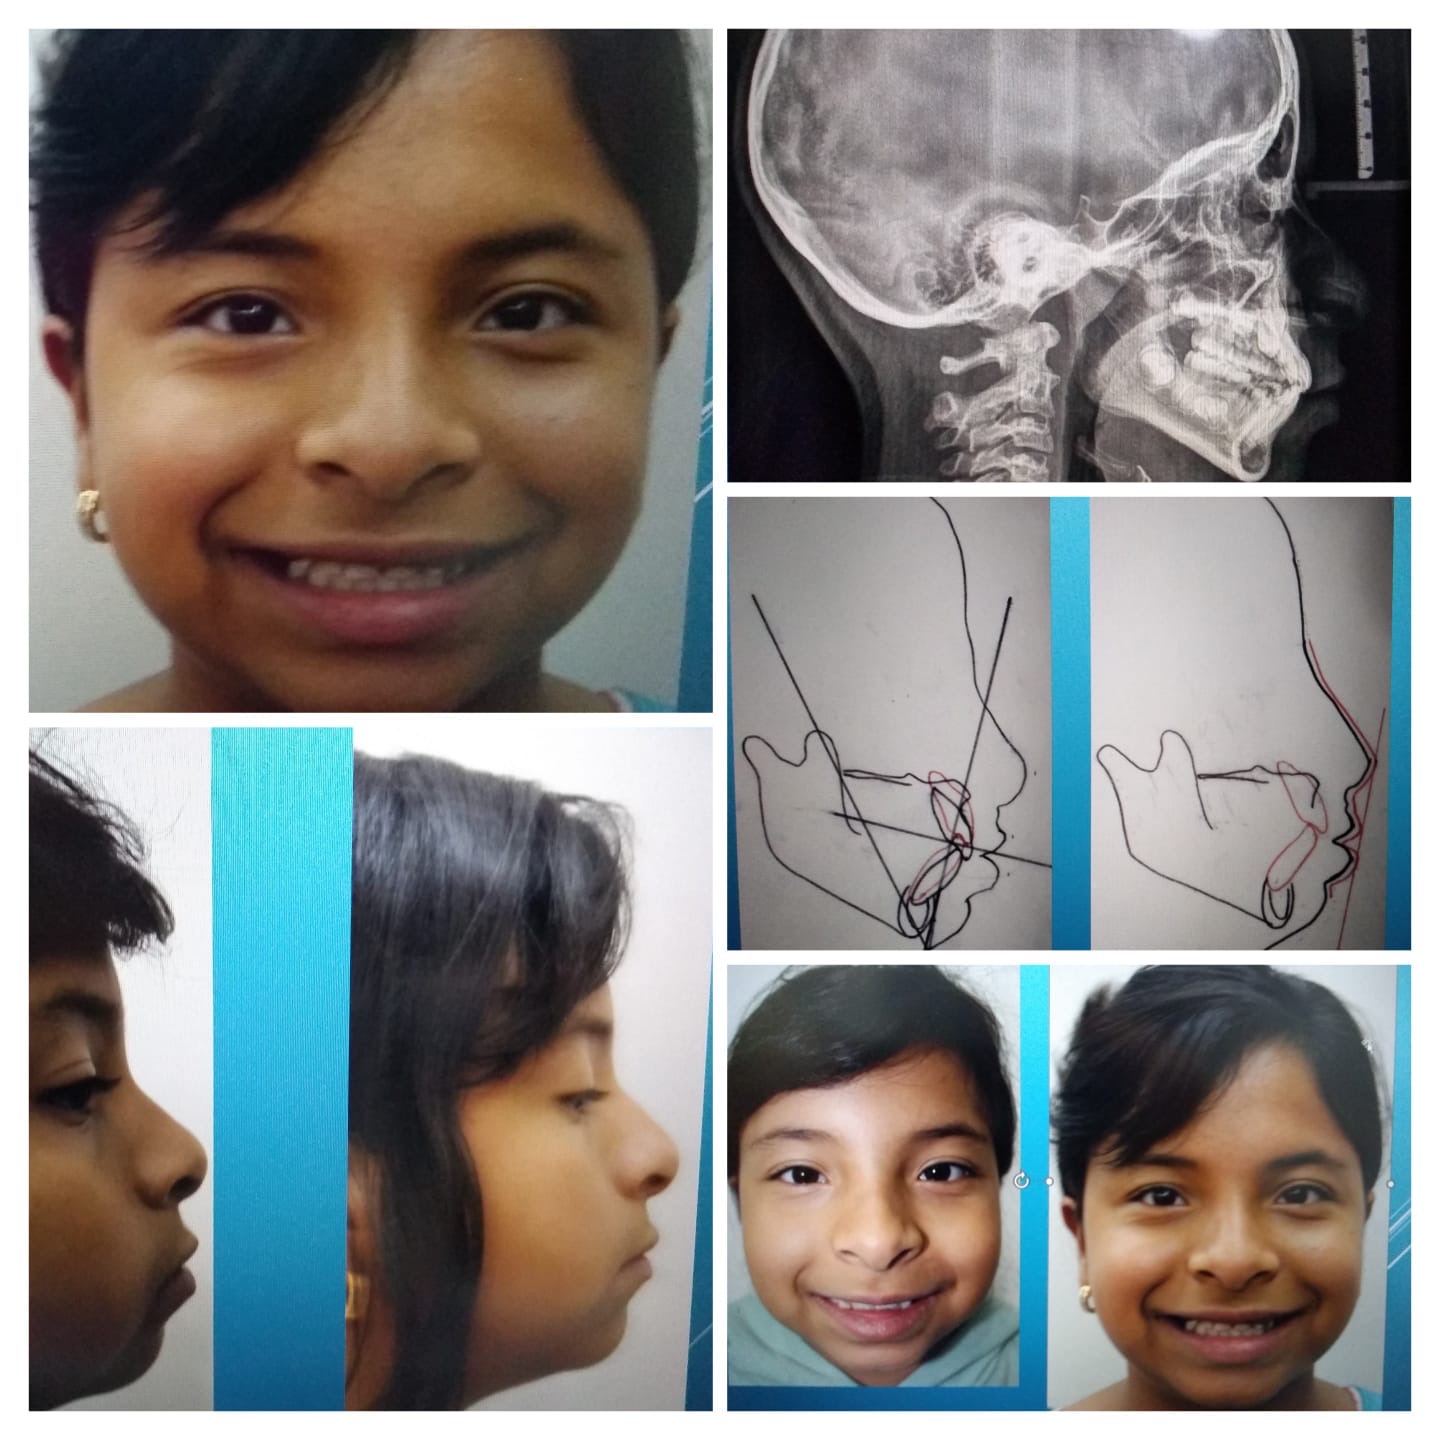

Ortodoncia

Especialistas en alineación y corrección dental, para una sonrisa perfecta.

Ortopedia Maxilar

Tratamientos correctivos de la estructura ósea facial, diseñados tanto para el desarrollo infantil como para la salud dental del adulto.

Ortodoncia y Ortopedia

Especialistas en el desarrollo óseo y alineación dental para niños, extendiendo nuestra experiencia en ortopedia maxilar también a pacientes adultos.

- Ortodoncia interceptiva y funcional.

- Ortopedia maxilar integral para el desarrollo correcto de la mordida.